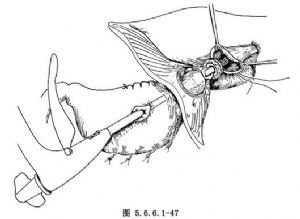

(8)将吻合器的装钉头从胃腔内对准上述小戳口,在中心杆上端旋紧抵钉座。经残胃大弯侧的戳口将中心杆插至吻合器主体机内,经食管裂孔将预定吻合的部分残胃推入左胸腔,然后将抵钉座插至食管近端管腔内(图5.6.6.1-47)。在向食管腔内插抵钉座时,动作要轻柔,因为食管口径的大小与抵订座的大小不相符时,可造成食管壁之撕裂。